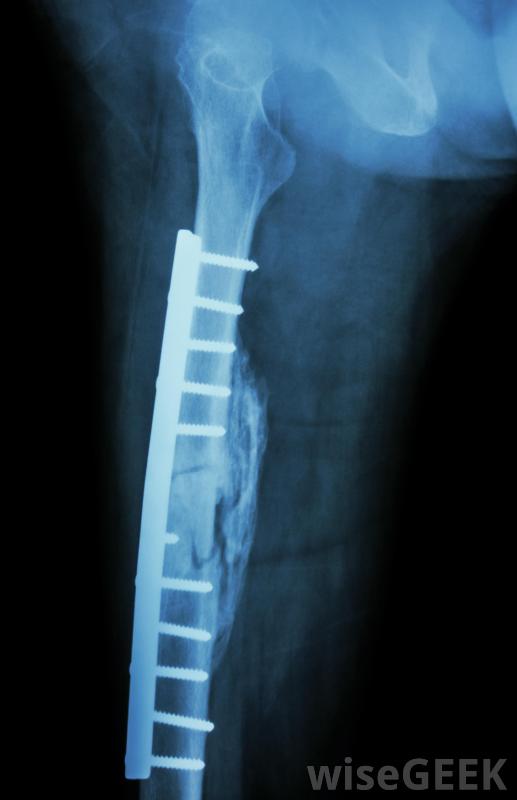

股骨钉是一种外科技术,用于治疗骨折或骨折的股骨,或股骨。该过程包括将一根称为髓内钉或股骨钉的金属棒插入股骨,并对其进行定位,使其沿着骨干的长度垂直运行。当钉穿过骨头的中部时,它起到将两个骨折段固定在一起,上下可放...

股骨钉是一种外科技术,用于治疗骨折或骨折的股骨,或股骨。该过程包括将一根称为髓内钉或股骨钉的金属棒插入股骨,并对其进行定位,使其沿着骨干的长度垂直运行。当钉穿过骨头的中部时,它起到将两个骨折段固定在一起,上下可放置螺丝钉固定,防止骨头绕棒旋转,与夹板或石膏相比,这种方法的优点是使股骨骨折迅速稳定,患者活动更快,避免长期不活动的并发症,例如腿部的血块。

股骨骨折固定手术在大多数情况下被称为扩髓股骨钉这包括沿着股骨的轴,穿过骨折部位,用X光检查它的位置。接下来,用一种被称为铰刀的切割工具为钉子掏出一条通道。最后,股骨钉插入骨头并固定到位。

股骨钉是一种借助X光片修复骨折股骨的手术。